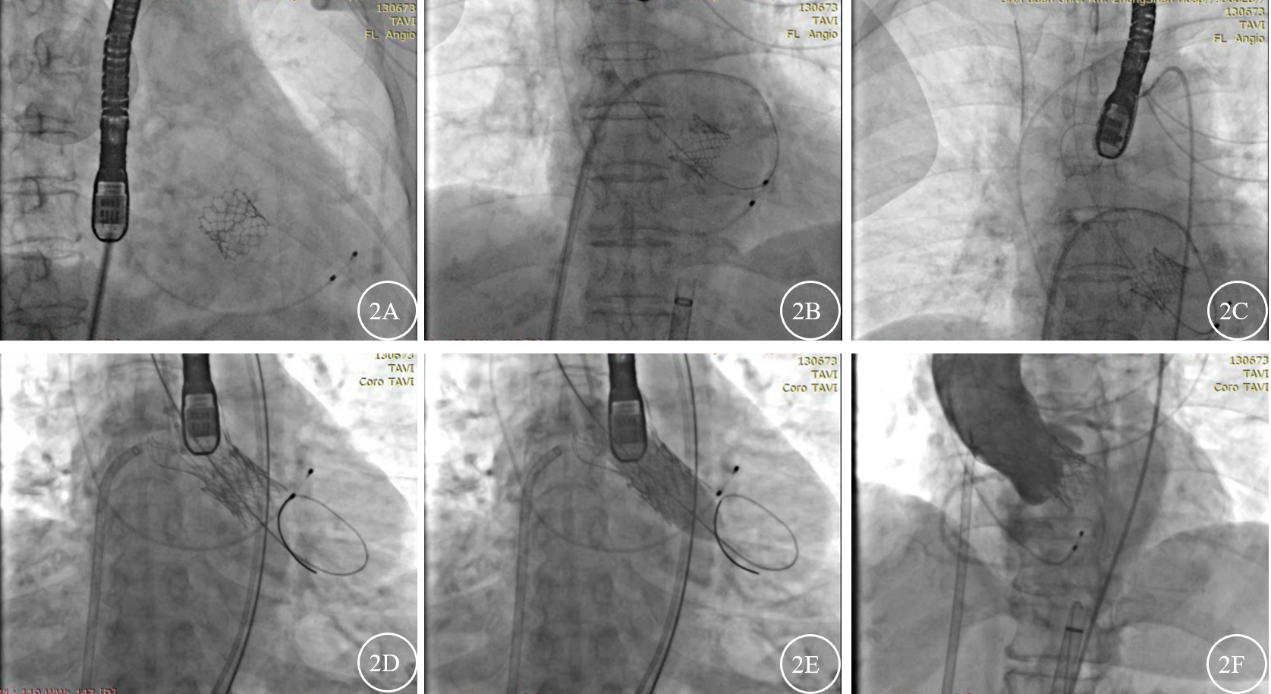

经心脏内科疑难病例讨论,患者目前考虑TAVR术后瓣膜衰败可能性大,与冠脉病变关联性小,决定再次行TAVR瓣中瓣植入手术。2020-12-16在杂交手术室行TAVR手术,手术采取经股动脉路径,全麻经食道超声心动图引导下进行。患者系TAVR术后瓣膜衰败重度主动脉瓣狭窄,导丝跨主动脉瓣难度大,三位术者轮流操作使用多种导丝一个小时均未能将导丝均未成功跨瓣。后遂决定尝试穿刺房间隔顺行跨瓣方法。2分钟完成穿刺房间隔穿刺,1分钟将导丝送入左心室并顺行通过主动脉瓣,3分钟在升主动脉将导丝套出体外成功建立轨道(图2)。结合术前CT和心超测量的瓣环直径大小,将装配好的21mm Vita-Flow主动脉瓣膜(上海微创心通医疗科技有限公司)经导丝从股动脉送至主动脉瓣环处,逐步释放瓣膜,跨瓣压差提示35mmHg,遂以球囊(VP-18040)于180bpm右心室起搏下进行后扩张1次,造影显示瓣膜位置良好后分离输送系统和瓣膜,术后即刻造影提示无瓣周漏、冠状动脉开口通畅,无瓣中反流(图2)。患者术后胸痛明显改善,顺利出院,出院前复查超声心动图示:TAVR术后,人工生物瓣跨瓣峰值压差40mmHg,未测及瓣周漏,目前患者规律随访中。

图2 患者接受经导管主动脉瓣置换术(TAVR)手术过程(2A为导丝正在穿刺房间隔;2B为导丝成功穿刺房间隔后,经左房、二尖瓣、左室到达升主动脉;2C为圈套器在升主动脉建立轨道;2D为成功建立轨道后人工瓣膜经股动脉路径逆行释放;2E为人工瓣膜释放后球囊扩张1次;2F为人工瓣膜成功释放后主动脉根部造影图,可见冠脉开口良好,无明显瓣周漏。